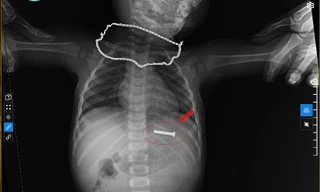

TPO - Trong lúc cả gia đình đang tất bật với công việc ngày cận Tết, bé 5 tuổi đã nuốt cục pin điện tử vào đường tiêu hóa, đối mặt với nguy cơ thủng ruột. Các bác sĩ đã tiến hành nội soi gắp thành công dị vật cho bệnh nhi.